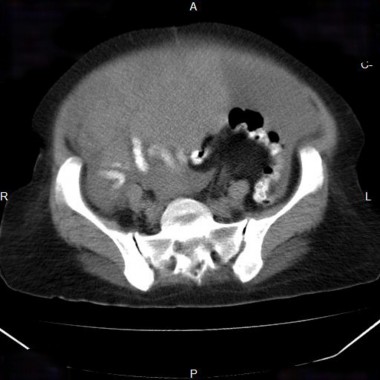

Cancer de l'ovaire avec carcinose péritonéale

Cancer de l’ovaire avec carcinose péritonéale

Case courtesy of Dr Ruslan Esedov, Radiopaedia.org. From the case rID: 7627